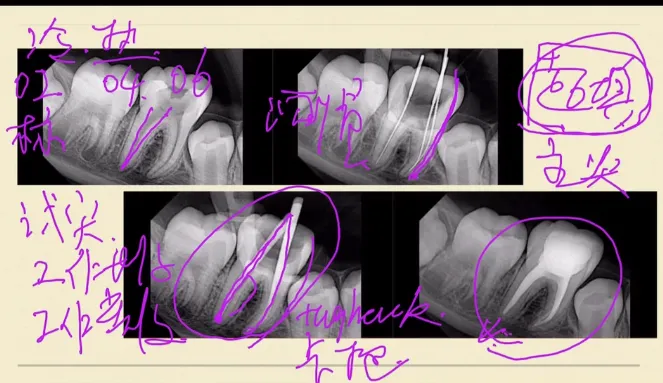

原片对于试尖片是非常的重要的。我们要试尖片要的是他工作的长度,我们还要去试它的尖端宽度。就是我们的主尖试进来之后,在我们的尖端是不是能形成一个卡抱感。只有这样形成一个很好的主尖形成一个很好的卡抱感。这个卡抱感的来源一定是来源于尖端,而不是上端的,这样我们才能最终形成一个很好的根充效果。才不会有超充问题发生。

我们试尖的时候,牙胶尖有卡抱感。就是说按照我们的工作长度,牙龈尖放进去之后,我们的牙胶尖能够紧紧的卡到根管里面去,这样回抽是有阻力的,就是它的卡包感,阻力的来源一定是来源于尖端的阻力,而不能是来源于你看上段中上段的阻力。

我们临床上在做热牙胶充填的时候,我们的主尖可能不容易卡到尖端,或者是不容易到达我们的根尖孔的位置上,那可能是由于我们的根备不足或者是有台阶,或者是根尖区的预备形态不规则,这些都是有可能可能的。所以说遇到这样的情况的时候,当你的主尖放入困难,或者是当你在根充的时候容易带出的时候,你就要考虑考虑你的预备也存在着问题,需不需要再次的一个预备成型,这种再次的预备成型主要针对于根尖的一个再次的预备和成型,成型好之后让我们的主尖能够紧紧的卡到我们的根尖去,让我们的牙胶的尖端能我们跟根管口的尖端有一个很好好的匹配性。